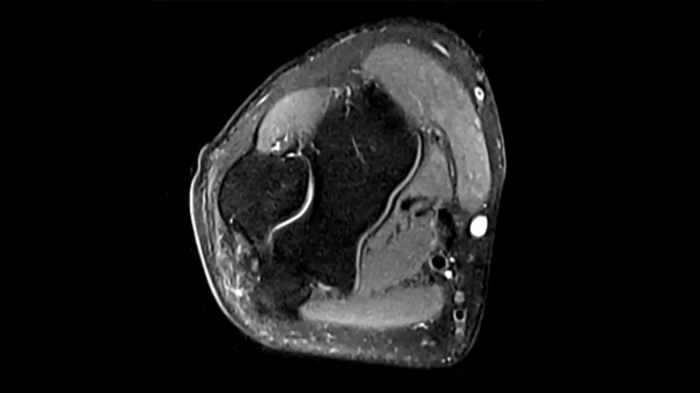

Knee

PD TSE Fat Sat with Deep Resolve and Simultaneous Multi-Slice

For clear imaging of the knee, outstanding fat suppression and performance are possible. Integrating the influence of Deep Resolve with the established Simultaneous Multi-Slice technique.

SMS 2 | Deep Resolve Gain & Sharp

0.4 x 0.4 x 3.0 mm2

TA 2:56 minutes

MAC-ID: 7aaaa0198. Image Credit: Siemens Healthineers

PD TSE Fat Sat with Deep Resolve and Simultaneous Multi-Slice

For clear imaging of the knee, brilliant fat suppression and performance are possible. Integrating the influence of Deep Resolve with the proven Simultaneous Multi-Slice technique.

SMS 2 | Deep Resolve Gain & Sharp

0.3 x 0.3 x 3.0 mm2

TA 2:16 minutes

MAC-ID: 7aaaa0198. Image Credit: Siemens Healthineers

T1 SE

Outstanding T1 imaging of the knee using MAGNETOM Free.Star.

0.3 x 0.3 x 3.0 mm2

TA 2:54 minutes

MAC-ID: 7aaaa0198. Image Credit: Siemens Healthineers

3D MSK Imaging with Compressed Sensing

Knee imaging with T2w SPACE can be expedited using Compressed Sensing to reduce acquisition times, offering high-resolution images for uncompromised knee assessments.

Compressed Sensing 6

0.3 x 0.3 x 0.6 mm2

TA 4:15 minutes

MAC-ID: 7aaaa0175. Image Credit: Siemens Healthineers